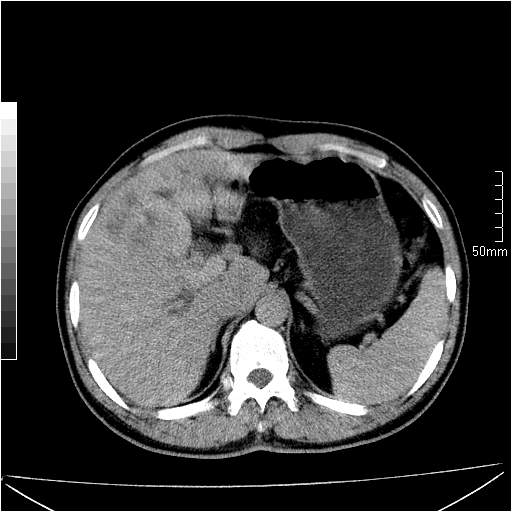

男性,54岁,皮肤黄染,搔痒一周余.b超示肝左叶回声异常.初步诊断1胆总管下段结石2胆囊结石伴慢性胆囊炎请各位战友帮忙看一下肝脏多发低密度如何解释恰当.增强效果不是很好.请大家见谅.

胆总管及肝内胆管扩张,考虑是结石!但,肝内的低密度区增强不明,可能是肝ca,因为肝ca在增强时呈快进快出.另年胆总管扩张原因,可以考虑一下是不是,胆管ca.再次要考虑肝内的低密度是否为海绵状血管瘤所致!

首先,胆总管下端结石梗阻伴肝内胆管扩张可确定。

其次,增强动脉期肝静脉显影,肝实质密度不均。——此为右心功能不全引起肝淤血的表现。

另外,肝八段低密度占位,呈多灶性,考虑肝脓肿或肝癌可能,(图像质量欠佳)建议进一步检查。

既然做了增强,为什么光提供延时期片子,肝动静脉期肝右叶前下段病灶增强如何?另外胆囊壁增厚,欠规整,内密度不均,与肝右叶病灶分界不清,增强表现怎样?肝内胆管轻度扩张,胆总管扩张,但未见明显结石影,也应提供增强早期图像才好鉴别扩张原因。片子较清,但不够完整,暂考虑1.胆囊癌肝局部浸润,或肝癌胆囊侵犯,2.胆总管下端或胰头钩突部占位。总之本人看不明白,请高手画图指示,先谢了!

由于胆囊窝内结构显示不清,肝脏病灶又邻近胆囊窝首先考虑胆囊癌肝受侵犯。而后因肝脏病灶强化有渐进改变,且相邻胆管扩张,故考虑肝胆管细胞癌待排。

左肝胆管细胞癌。

胆总管下端结石。